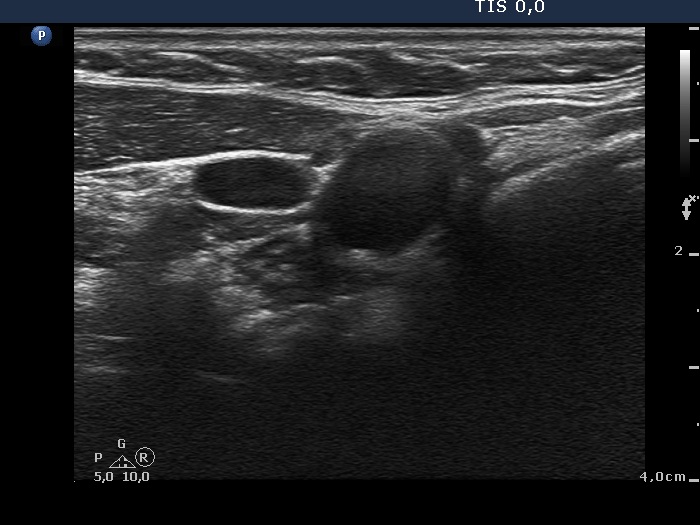

Ultrasonography. The right thyroid was moderately hypoechogenic without any circumscribed lesions. The left thyroid was removed. There were several enlarged lymph nodes in the right submandibular area. The largest one presented two discrete, more hypoechogenic intranodal lesions and a regular hilum.

Comment. This is an unusual case, the nodes (particularly those presented in the video) seem to be benign, reactive-type ones.